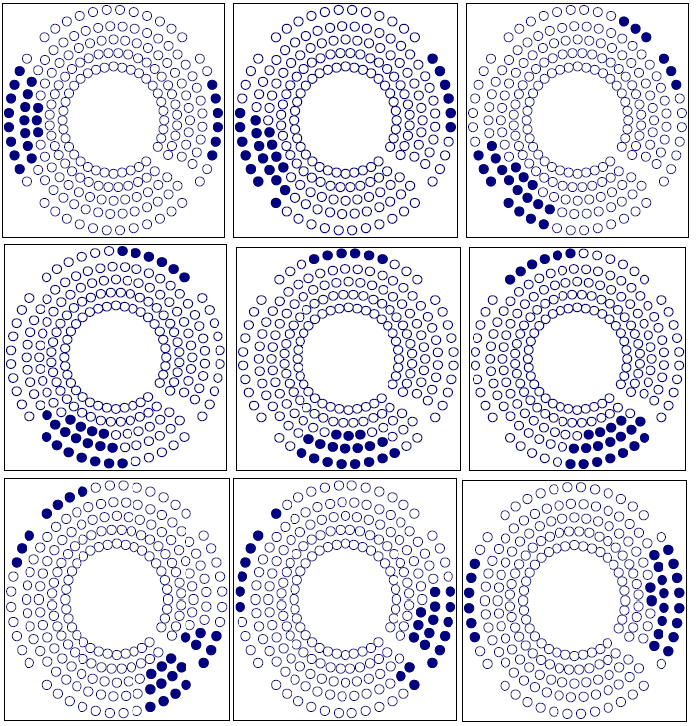

Figure 7 shows the sample point effect on the integral dose calculation by three different trials. The calculation converges at about 100,000 sample points. The number of sample points is determined using an exponential formula. In this setup, we used the integral dose that was calculated by the Monte Carlo method to test the target variation effect on the treatment plan. The Gamma Knife treatment planning system was selected due to the fixed number of beams (201) and fixed geometry of those beams. After checking the convergence of the Monte Carlo calculation, we employed this method to show the sensitivity of the integral dose in beam selection. We fabricated a nine shot Gamma Knife treatment plan with the shot centers midway between inside and outside rings. With a sequence blocking beam treatment for each shot selected, 24 beams were selected to block. There are different possibilities for target variation. A typical case would be the displacement of a target such as an organ at risk. Figure 8 shows three different blocking patterns. Figure 8(a) shows an original setup with 9 plugging shots. Figures 8(b) and 8 (c) show the plugging patterns after the critical structure has been shifted 2 mm superiorly or inferiorly. We developed several mechanisms to compare the different plugging patterns in both the DVH's and treatment patterns. In figure 9, the upper DVH shows the difference due to structure displacement. The circles represent the DVH of the critical region without displacement. The triangles represent the DVH resulting when the critical region is shifted superiorly 2 mm, and the squares represent the situation when the critical region is shifted inferiorly 2 mm. When a blocking beam pattern is used for the treatment, the DVH curves show two features: in one, the dose in the critical structure is significantly lower; in the other, the difference in the three DVH curves decreases and DVH curves nearly overlap each other due to selection of blocking beams. Obviously, displacement of the target leads to variation in the treatment setup. The target DVH curves are not shown because they are overlapped and almost identical for the given resolution in figure 9.

Figure 8a Plugging Pattern of a 9 shot treatment without displacement of the critical structure.

Figure 8b Plugging Pattern of a 9 shot treatment with the critical structure displaced 2 mm superiorly.

Figure 8c Plugging Pattern of 9 shots treatment with the critical structure displaced 2 mm inferiorly.